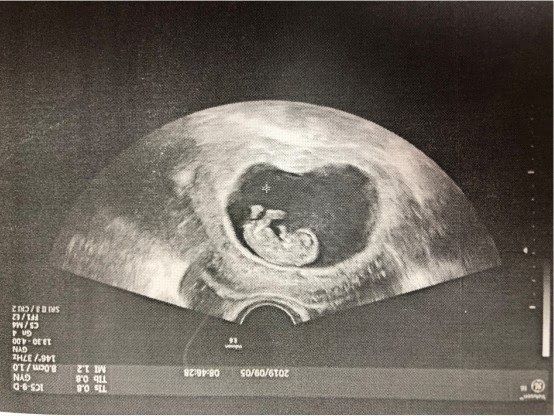

于是徐芬医生当机立断,决定更改患者方案,采用直促方案,适当增加LH的补充,期间密切监测孙女士的血激素变化。经过整改方案积极促排之后,最终孙女士获取到10多枚卵子,移植2枚D3天胚胎,现已成功妊娠!